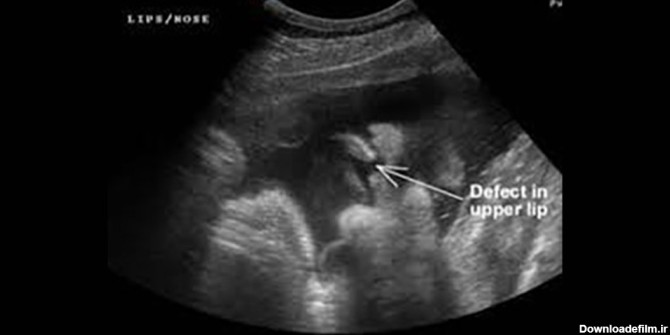

عکس سونو جنین لب شکری

شکاف کام | عکس جنین لب شکری در سونوگرافی

امکان شناسایی جنین مبتلا به لب شکری از طریق سونوگرافی

امکان شناسایی جنین «لب شکری» با سونوگرافی

عکس جنین لب شکری

عکس سونوگرافی جنین لب شکری

عکس جنین لب شکری در سونوگرافی